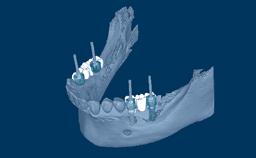

Prosthodontic Planning and Procedures

Implant Configurations for Fixed Dental Prostheses

Learning Module